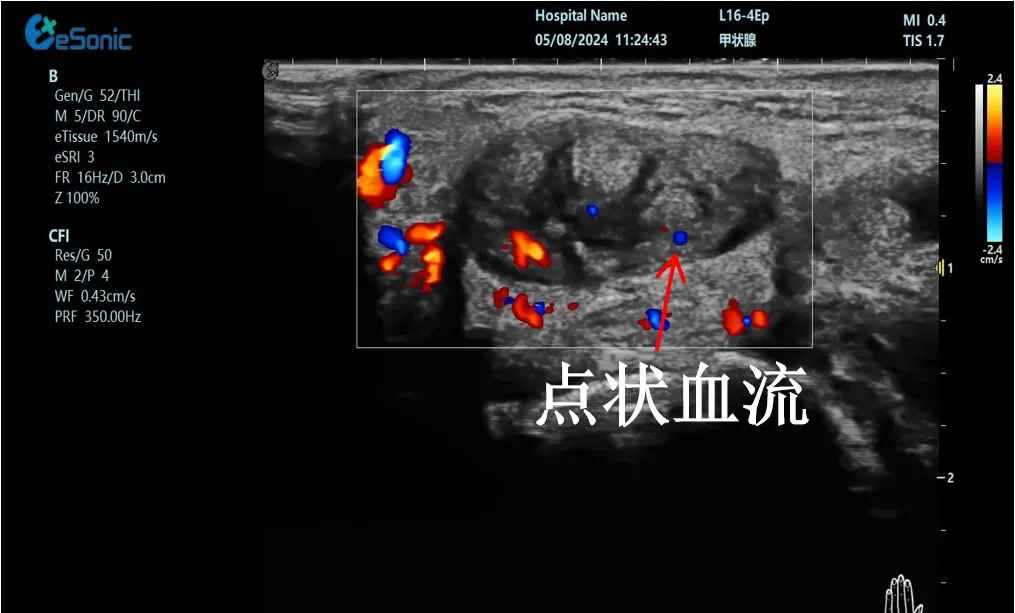

mFlow?技术在腱鞘炎诊疗中的应用

【背景】:左手腕关节第四腔室腱鞘炎。

【痛点】:普通彩色多普勒不敏感,只能看到细小点状血流,容易被忽略,难以进行分级诊断和疗效评估。

【方案】:利来国国际网站医疗(ESI)超微血流技术可以看到腔室内肌腱周围环状血流,可充分提示:

1、处于炎症活动期;

2、根据血流进行分级诊断提示1级;

3、治疗后根据血流多少评估疗效(见右下图:治疗10天后复查超声,微血流图像血供消失)。